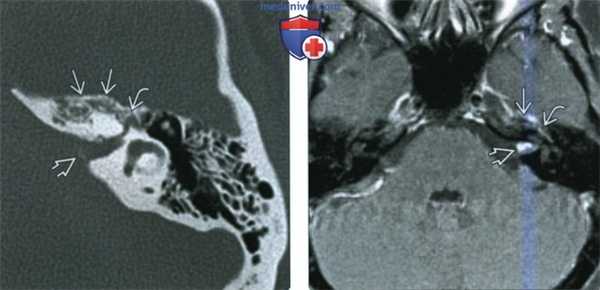

(Слева) При аксиальной МРТ Т1 ВИ С+ у пациента с парезом лица определяется С+ ШЛН с поражением ММУ, ВСК, лабиринтного сегмента, коленчатого ганглия ЧН VII. Если ШЛН ограничена ВСК, она в точности напоминает вестибулярную шванному.

(Справа) При аксиальной тонкосрезовой МРТ Т2 с увеличением в области дна ВСК слева у пациента с нейрофиброматозом 2 типа визуализируются шванномы верхнего преддверного и лицевого нервов. Внимание: при НФ2 не все опухоли в ВСК являются шванномами.